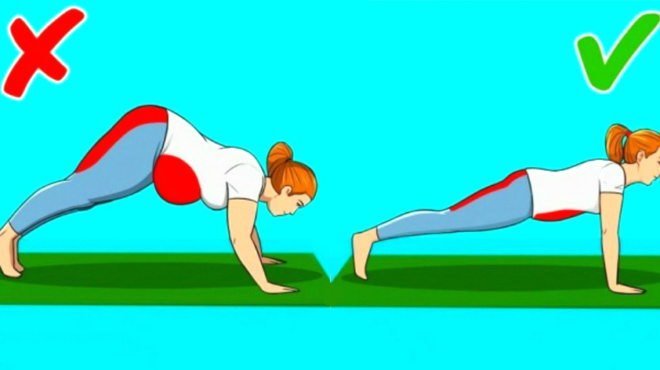

Άσκηση

Με προσοχή βέβαια στο τι θα κάνετε, για να μην καταλήξετε τελικά να τα καταπονήσετε περισσότερο. Δηλαδή, σαφώς και αποφεύγετε γυμναστικές τύπου crossfit ή έντονο ποδήλατο. Αντίθετα το κολύμπι, το περπάτημα και σε κάποιες περιπτώσεις το ελλειπτικό, βοηθούν ιδιαίτερα στην εκγύμναση των τετρακέφαλων (οι μύες που στηρίζουν τα γόνατα), χωρίς να τα επιβαρύνουν.

Προτεινόμενες ασκήσεις

Έκταση του γόνατος ενώ είστε καθιστοί (με κίνηση)

Καθίστε ευθυτενείς σε μια καρέκλα και ακουμπήστε τα πόδια σας στο πάτωμα. Σιγά-σιγά σηκώστε και ισιώστε το πόδι που σας πονά μέχρι να νιώσετε τους μηρούς σας να σφίγγουν. Κρατήστε το πόδι σας σε αυτή τη θέση και ύστερα επιστρέψετε στην αρχική θέση. Επαναλάβετε την άσκηση 10 φορές.

Ενδυνάμωση τετρακεφάλων Σφίξτε τους μυς που βρίσκονται πάνω από το γόνατό σας πιέζοντας το πίσω μέρος των γονάτων σας στο κρεβάτι. Η πτέρνα θα πρέπει να σηκώνεται από το κρεβάτι. Τυχόν νάρθηκες μπορούν να παραμείνουν. Μείνετε για 10 δευτερόλεπτα. Επαναλάβετε 10 φορές, 3 φορές ημερησίως.